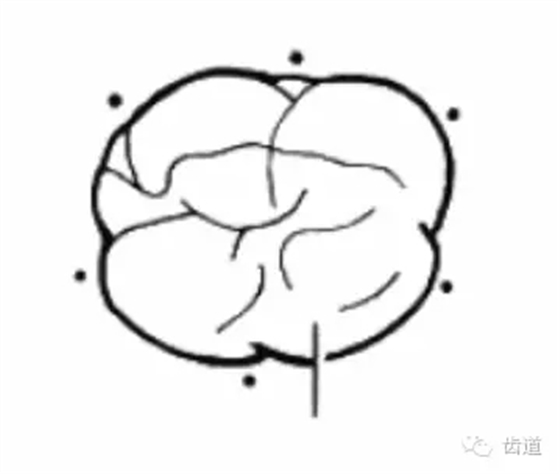

根分叉病變

工具:彎探針(Nabers探針),頂端為鈍頭,有刻度,(可用彎尖探針代替)

方法:下頜磨牙,頰舌側(cè)中央探查;上頜磨牙,頰側(cè)中央及腭側(cè)近遠中探查

內(nèi)容:

分度:Glickman分度標(biāo)準(zhǔn)

Furcation

Furcation involvement